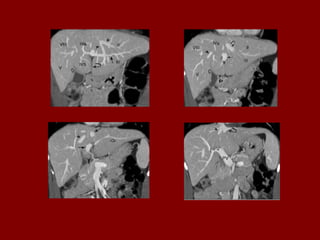

Ac Colo ascendente AP Nível de ar fluido do estômago Ao Aorta Az Veia ázigo CA Tronco celíaco cc Cartilagem costa! CD Dueto cístico CHA Artéria hepática comum CHD Dueto comum CL Lobo caudado fígado D Diafragma DBM Músculos profundos do De Colo descendente D2 Parte descendente do duodeno D3 Parte horizontal do duodeno E Esôfago FL Ligamento falciforme GB Vesícula biliar HA Artéria hepática Hz Veia IMV Divisão da veia mesentérica inf. A IVC Veia cava inferior LC Ramo esq. do diafragma LG Glândula supra-renal esq. LHV Veia hepática esquerda LIL Lobo inf. Esq. do pulmão LRV Veia renal esquerda LK Rim esquerdo LU Ureter esquerdo LL Lobo esquerdo do fígado MHV Veia hepática média P Pâncreas PA Antro pilórico do estômago

Ac Colo ascendente AP Nível de ar fluido do estômago Ao Aorta Az Veia ázigo CA Tronco celíaco cc Cartilagem costa! CD Dueto cístico CHA Artéria hepática comum CHD Dueto comum CL Lobo caudado fígado D Diafragma DBM Músculos profundos do De Colo descendente D2 Parte descendente do duodeno D3 Parte horizontal do duodeno E Esôfago FL Ligamento falciforme GB Vesícula biliar HA Artéria hepática Hz Veia IMV Divisão da veia mesentérica inf. IVC Veia cava inferior B LC Ramo esq. do diafragma LG Glândula supra-renal esq. LHV Veia hepática esquerda LIL Lobo inf. Esq. do pulmão LRV Veia renal esquerda LK Rim esquerdo LU Ureter esquerdo LL Lobo esquerdo do fígado MHV Veia hepática média P Pâncreas PA Antro pilórico do estômago

Ac Colo ascendente AP Nível de ar fluido do estômago Ao Aorta Az Veia ázigo CA Tronco celíaco cc Cartilagem costa! CD Ducto cístico CHA Artéria hepática comum CHD Ducto comum CL Lobo caudado fígado D Diafragma DBM Músculos para vertebrais De Colo descendente D2 Parte descendente do duodeno D3 Parte horizontal do duodeno E Esôfago FL Ligamento falciforme GB Vesícula biliar HA Artéria hepática Hz Veia IMV Divisão da veia mesentérica inf. C IVC Veia cava inferior LC Ramo esq. do diafragma LG Glândula supra-renal esq. LHV Veia hepática esquerda LIL Lobo inf. Esq. do pulmão LRV Veia renal esquerda LK Rim esquerdo LU Ureter esquerdo LL Lobo esquerdo do fígado MHV Veia hepática média P Pâncreas PA Antro pilórico do estômago

Ac Colo ascendente AP Nível de ar fluido do estômago Ao Aorta Az Veia ázigo CA Tronco celíaco cc Cartilagem costa! CD Dueto cístico CHA Artéria hepática comum CHD Dueto comum CL Lobo caudado fígado D Diafragma DBM Músculos profundos do De Colo descendente D2 Parte descendente do duodeno D3 Parte horizontal do duodeno E Esôfago FL Ligamento falciforme GB Vesícula biliar HA Artéria hepática Hz Veia IMV Divisão da veia mesentérica inf. D IVC Veia cava inferior LC Ramo esq. do diafragma LG Glândula supra-renal esq. LHV Veia hepática esquerda LIL Lobo inf. Esq. do pulmão LRV Veia renal esquerda LK Rim esquerdo LU Ureter esquerdo LL Lobo esquerdo do fígado MHV Veia hepática média P Pâncreas PA Antro pilórico do estômago